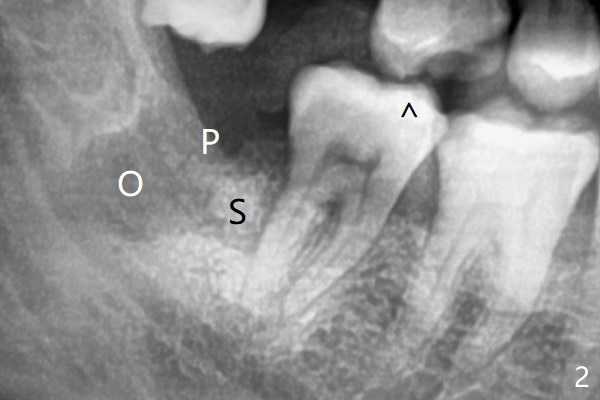

为了顺利成骨(与方炳忠医生根管治疗之后调整咬合一致),拔除智齿前,对第二磨牙近中颊侧咬合面进行降低(图二:箭头)。为了止血和减少骨粉使用量,牙槽窝远中放置胶原骨(Osteogen Plug,O),而第二磨牙远中放置粘性骨粉(sticky bone (allograft),S),后者也是必须的,因为在炎症期间,拔除智齿,出血,即使不严重,一般骨粉容易被血冲走。下次植骨前牙槽窝必须放置含肾上腺素纱布止血,上面加干纱布。最后牙槽窝表面放置两块PRF膜(P),严密缝合。